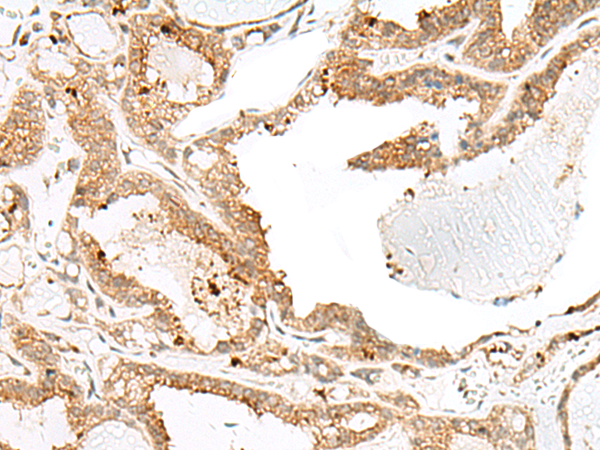

分类: 科研抗体货号: P06610别名: ENA; MENA; NDPP1应用: IHC反应种属: Human, Mouse